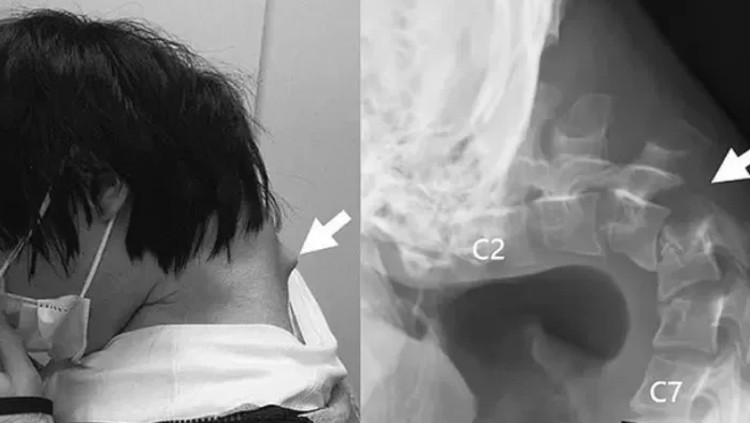

צוואר שבור, כיסא גלגלים וניתוחים קשים: הסכנות של גלילה ממושכת בטלפון